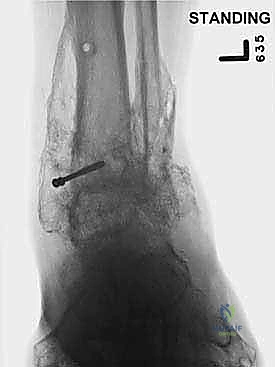

- الأشعة السينية أثناء الوقوف (Weight-bearing X-rays): هي الفحص الذهبي والأهم. يجب أن تؤخذ الأشعة والمريض واقف لتحمل الوزن. تظهر الأشعة تضيق المسافة المفصلية (دليل على فقدان الغضروف)، وجود نتوءات عظمية، تصلب العظم، وأي انحراف في محور المفصل.

- التصوير المقطعي المحوسب (CT Scan): يطلبه الدكتور هطيف لتقييم جودة العظام (Bone stock)، تحديد حجم الأكياس العظمية، ورسم خريطة ثلاثية الأبعاد للتشوهات المعقدة قبل الجراحة.